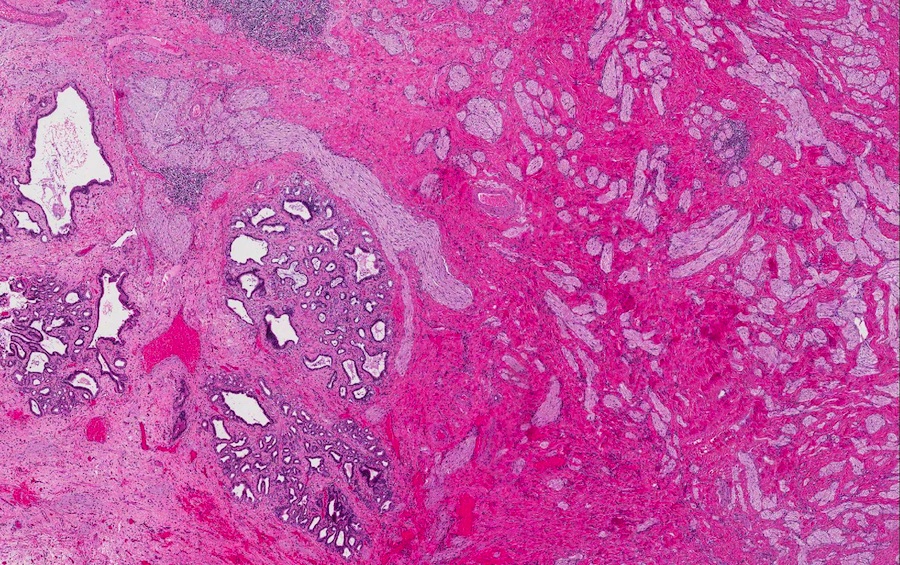

Microscopic images:

Microscopic images:

Both cases showed disorganized and thickened nerve bundles composed of spindle shaped cells, without atypia. Case A also showed a focal foreign body type giant cell reaction adjacent to the disorganized nerve bundles and a strongly immunoreactive S100 stain.

Histology typically shows hyperplastic nerve bundles, positive for S100.

Microscopic images:

Microscopic images:

Both cases showed disorganized and thickened nerve bundles composed of spindle shaped cells, without atypia. Case A also showed a focal foreign body type giant cell reaction adjacent to the disorganized nerve bundles and a strongly immunoreactive S100 stain.

Histology typically shows hyperplastic nerve bundles, positive for S100.